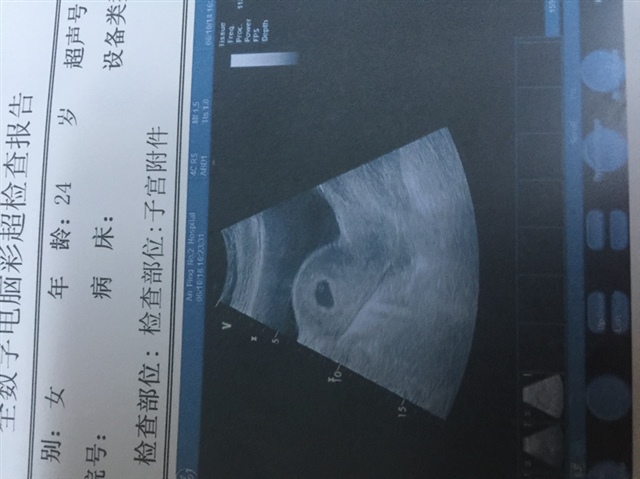

我花了70找熟人,是女宝

孕10周+2天

女宝